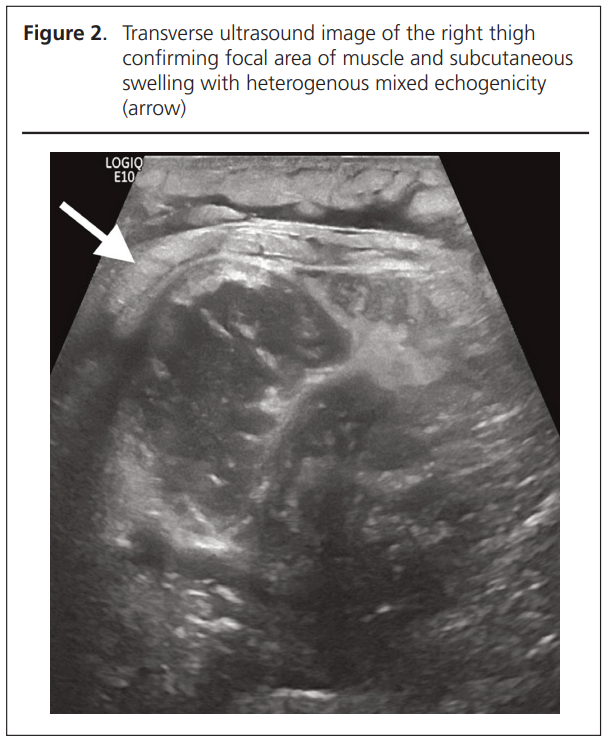

Ultrasound Doppler of the right thigh excluded a focal collection and above-knee deep vein thrombosis (DVT) but did show focal muscle swelling (Figure 2). Magnetic resonance imaging (MRI) of both thighs confirmed unilateral extensive right medial compartment muscle swelling, myositis and ischaemia. This was most severe in portions of the sartorius, adductor longus and vastus intermedius. There was no focal soft tissue or osseous collection, marrow infarct or osteomyelitis (Figures 3 and 4).